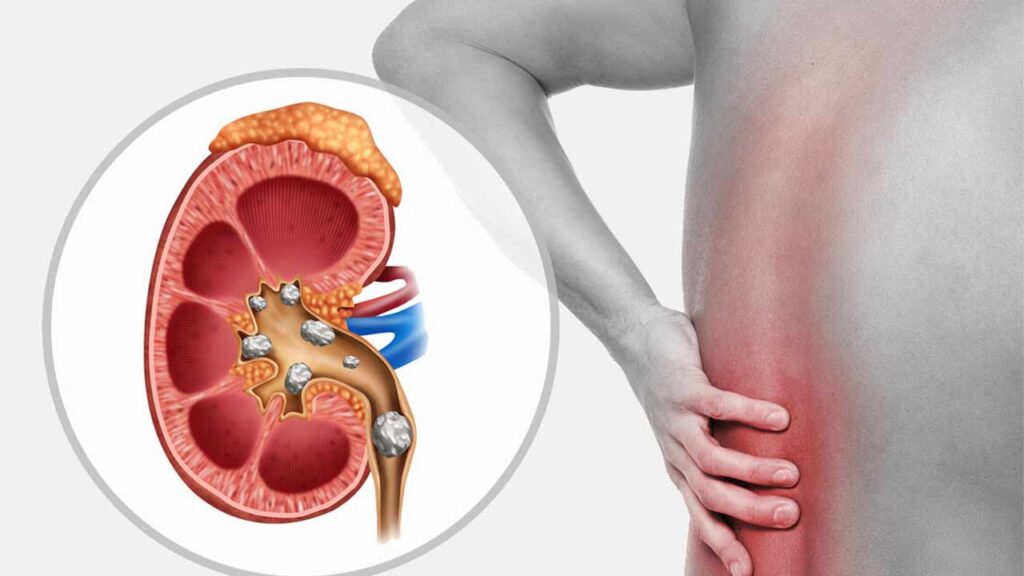

302 - این کارها باعث ایجاد سنگ کلیه می شود

اینتیتر- پزشکی- 16 ماه پیش - شنبه 16 دی 1402، 12:18 70809695

اینتیتر- پزشکی- 16 ماه پیش - شنبه 16 دی 1402، 12:18 70809695

سنگ های کلیه رسوباتی سخت از جنس مواد معدنی (کلسیم، اگزالات و فسفات) هستند که در کلیه های شما تشکیل می شوند. ابتلا به سنگ کلیه دلایل زیادی دارد و می تواند هر بخشی از دستگاه ادراری شما از ...

303 - این کارها باعث ایجاد سنگ کلیه می شود

صد آنلاین- پزشکی- 16 ماه پیش - شنبه 16 دی 1402، 09:53 70806872

صد آنلاین- پزشکی- 16 ماه پیش - شنبه 16 دی 1402، 09:53 70806872

صد آنلاین | سنگ های کلیه رسوباتی سخت از جنس مواد معدنی (کلسیم، اگزالات و فسفات) هستند که در کلیه های شما تشکیل می شوند. ابتلا به سنگ کلیه دلایل زیادی دارد و می تواند هر بخشی از دستگاه ...

305 - این عادت های غلط سنگ کلیه می سازند

آفتاب- پزشکی- 16 ماه پیش - چهارشنبه 13 دی 1402، 20:40 70781791

آفتاب- پزشکی- 16 ماه پیش - چهارشنبه 13 دی 1402، 20:40 70781791

سنگ های کلیه رسوباتی سخت از جنس مواد معدنی (کلسیم، اگزالات و فسفات) هستند که در کلیه های شما تشکیل می شوند. ابتلا به سنگ کلیه دلایل زیادی دارد و می تواند هر بخشی از دستگاه ادراری شما از ...

306 - علائم سنگ کلیه؛ چند علامتی که نباید از آن غافل شوید!

ریمینو- پزشکی- 16 ماه پیش - سه شنبه 12 دی 1402، 00:34 70754917

ریمینو- پزشکی- 16 ماه پیش - سه شنبه 12 دی 1402، 00:34 70754917

منبع ریمینو در ادامه اصلی ترین علائم سنگ کلیه را توضیح داده ایم. سنگ کلیه یکی یکی از بیماری های شایع دستگاه ادراری و سیستم دفع مواد زائد بدن است. - در ادامه اصلی ترین علائم سنگ کلیه را ...

صد آنلاین | سنگ کلیه، تشکیل سنگ در کلیه، یکی از قدیمی ترین و شناخته شده ترین بیماریها در دستگاه ادراری با میزان عود 50 درصد50در بازه زمانی 5 تا 10 سال است. - به گزارش صد آنلاین ، سنگ کلیه ...